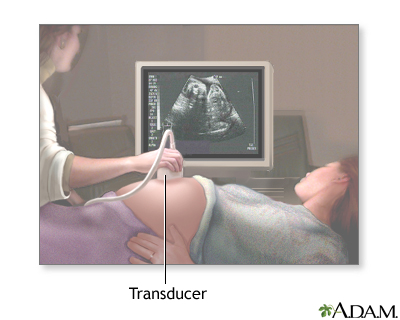

Your health care provider can diagnose this condition with a pregnancy ultrasound.